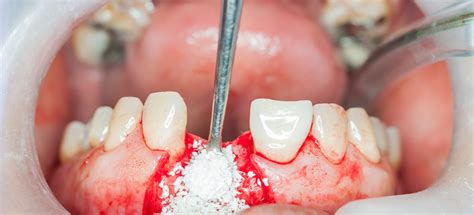

- Procedimiento quirúrgico: se realiza una incisión en las encías, se coloca el injerto y se cierra la zona tratada.

Llegada la fecha de la operación, sus manos expertas han de efectuar un corte en la zona donde debe ir el injerto. A continuación, se coloca una membrana que cubre la operación y que impide que se pierda el implante, y se cose la encía. Técnicamente hablando, no existen síntomas de rechazo del injerto porque los materiales empleados son biocompatibles con tu cuerpo. Al ser la zona donante parte del tejido de la propia persona, no hay en ningún caso problemas de rechazo.